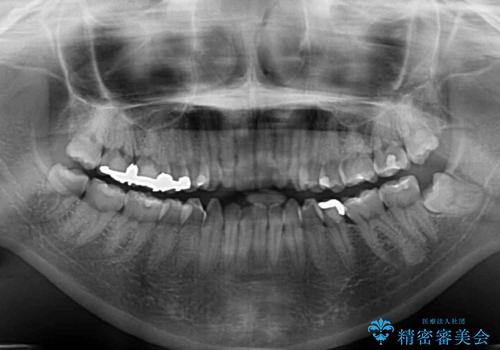

- 前歯のデコボコを気にして来院された患者様です。

下顎が骨格的にずれており、上下正中を合わせることは難しいことが予想されたため、デコボコの解消を主目的として、ワイヤー矯正を行うこととしました。